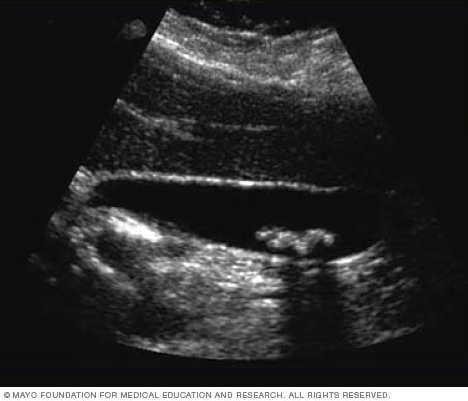

Ultrasound of gallstones

This ultrasound shows gallstones in the gallbladder.